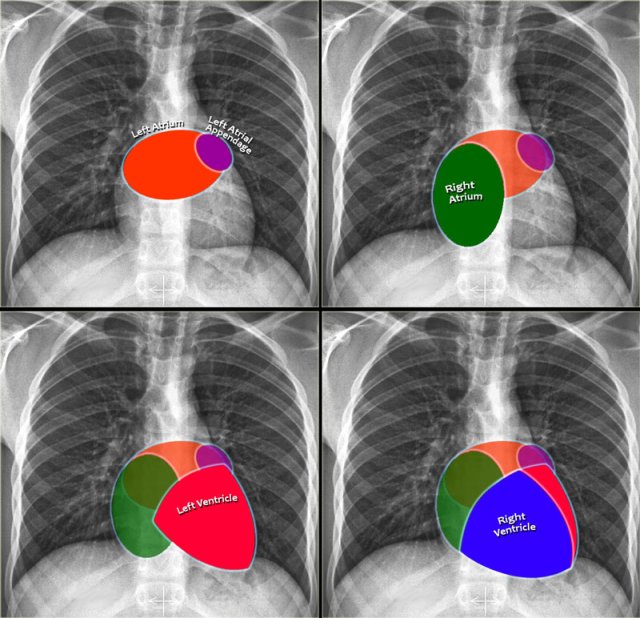

Heart and Pericardium

On a chest film only the outer contours of the heart are seen.

In many cases we can only tell whether the heart figure is normal or enlarged and it will be difficult to say anything about the different heart compartments.

However it can be helpful to know where the different compartments are situated.

Left Atrium

- Most posterior structure.

- Receives blood from the pulmonary veins that run almost horizontally towards the left atrium.

- Left atrial appendage (in purple) can sometimes be seen as a small outpouching just below the pulmonary trunk.

- Enlargement of the left atrium results on the PA-view in outpouching of the upper heart contour on the right and an obtuse angle between the right and left main bronchus. On the lateral view bulging of the upper posterior contour will be seen.

Right Atrium

- Receives blood from the inferior and superior vena cava.

- Enlargement will cause an outpouching of the right heart contour.

Left Ventricle

- Situated to the left and posteriorly to the right ventricle.

- Enlargement will result on the PA-view in an increase of the heart size to the left and on the lateral view in bulging of the lower posterior contour.

Right Ventricle

- Most anterior structure and is situated behind the sternum.

- Enlargement will result on the PA-view in an increase of the heart size to the left and can finally result in the left heart border being formed by the right ventricle.

- The upper posterior border of the heart is formed by the left atrium.

- Enlargement will result in bulging of the upper posterior contour

- Forms the lower posterior border.

- Enlargement will displace the contour more posteriorly.

- The lower retrosternal space is filled by the right ventricle.

- Enlargement of the right ventricle will result in more superior filling of this retrosternal space.